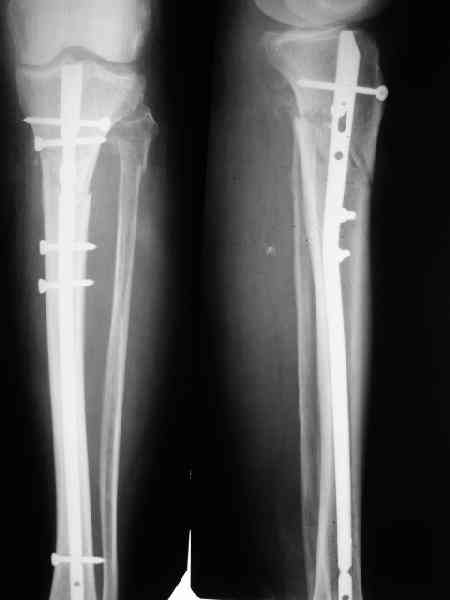

рассверливание костно-мозгового канала, реостеосинтез штифтом UFN (при проведении штифта в дистальном отломке мы использовали поляризующий винт, диаметр штифта 10 мм). После операции в связи гемартрозом дважды (на 1 и 3 сутки) выполняли пункцию коленного сустава. Сейчас признаков скопления жидкости в полости сустава нет. Послеоперационные рентгенограммы - images 5, 6, 7.

Все здорово! Но, 1)- почему штифт 10мм, а не больше?, 2) - проксимальное блокирование одним вмнтом в статическом положении?

2) По-поводу проксимлаьного блокирующего винта. Винт стоит на 3-5 мм выше нижнего

края динамического отверстия. Препятствий для компрессии отломков пока нет.